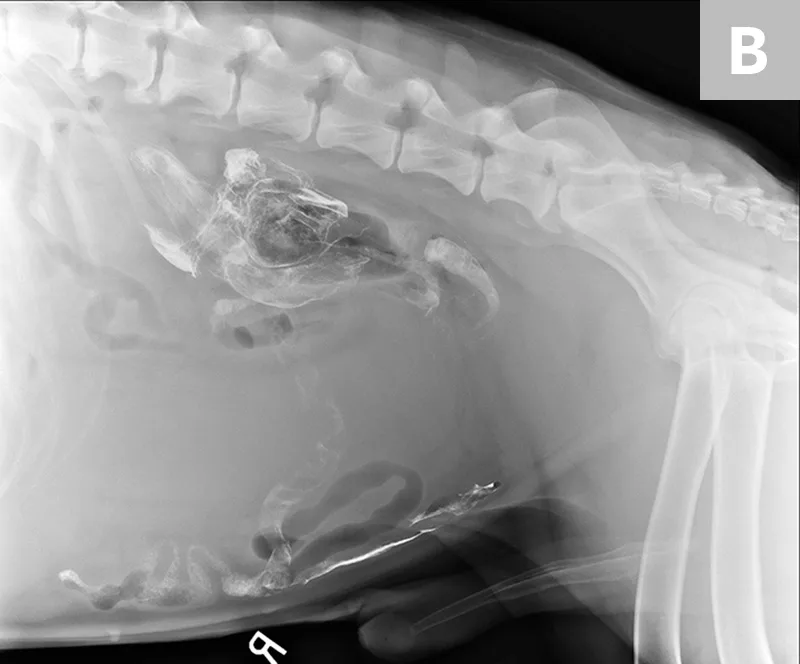

Treatment of the underlying disease in these conditions may relieve or reduce splenomegaly. In cases of splenic torsion (Figures 5 and 6), splenectomy is the recommended treatment, with approximately 90% of dogs surviving to discharge.19

FIGURE 5

Splenic torsion appears as a large soft-tissue opacity that displaces the GI tract caudally and peripherally (A). The splenic head is obscured caudal to the left margin of the stomach (B). The metallic opacity seen in the stomach and intestines is caused by recent barium administration.